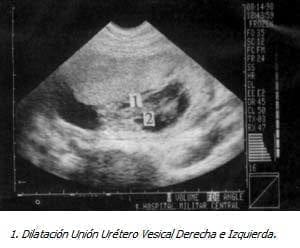

Con Impresión Diagnóstica de dolor abdominal a estudio y embarazo de 18 semanas se realiza ecografía obstétrica que evidencia feto único, vivo, con biometría para 18 semanas, ausencia del líquido amniótico y distensión abdominal importante. Se realizó ecografía de detalle previa cordocentesis para cariotipo y amnioinfusión de SSN, observando marcada ascitis, dilatación vesical importante con engrosamiento de la pared y dos soluciones de continuidad, dilatación de la uretra proximal y aumento de tamaño e hiperecogenicidad renal bilateral, los ureteres no se evidenciaron excepto en la unión vesicoureteral. El resultado del estudio genético confirmó sexo masculino (46XY) sin ninguna malformación genética asociada.

La obstrucción del nivel uretral secundario a valvas posteriores tiene un amplio espectro de características ecográficas y los signos cardinales consisten en dilatación persistente de la vejiga y la porción proximal de la uretra, engrosamiento de la pared vesical mayor de 2mm, los uréteres están característicamente dilatados y tortuosos y en casos severos su entrada a la vejiga se observa (10-15).